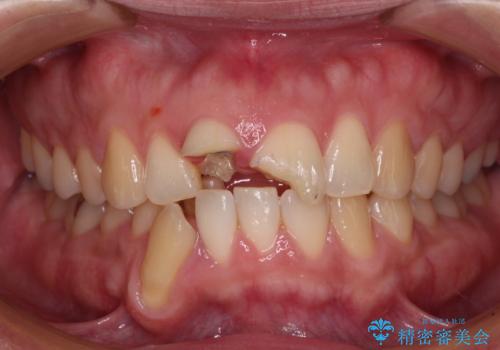

- 転倒により前歯を折ってしまったとのことで来院された患者様です。

右側の前歯は歯茎の中にまで及ぶ深い破折線があり、神経組織は既に失活していました。

左側の前歯は大きく歯冠が欠けてはいましたが、神経の生活反応が認められました。